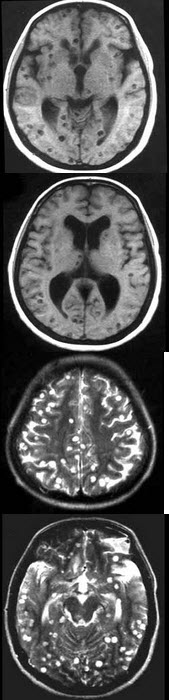

男,43岁,头痛半年余,MRI检查如图,最可能的诊断为( )

A:脑梗死

B:多发性结节硬化

C:转移瘤

D:脑实质型脑囊虫

E:脑囊肿